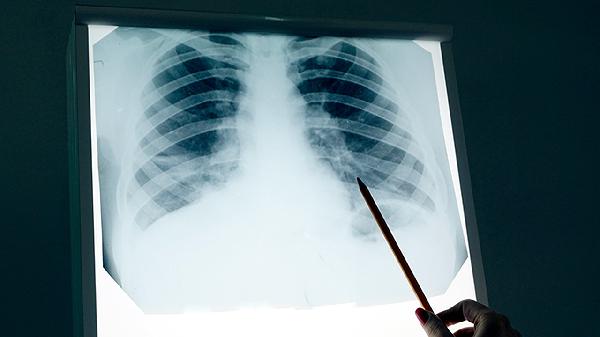

发现纵隔占位或肺部阴影时,应及时进行胸部CT、病理活检等检查明确诊断。日常生活中需避免吸烟及二手烟暴露,注意空气质量,定期体检有助于早期发现病变。确诊后应严格遵循医嘱选择个体化治疗方案,不同性质的肿瘤在饮食调理和康复训练方面也存在差异。